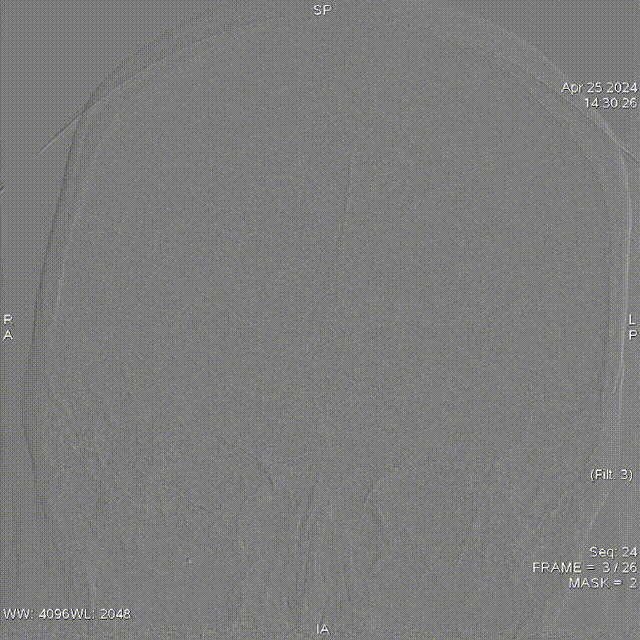

影像学资料

急诊头颅CT:无明显脑梗死、脑出血征像。

弓造影

左侧前循环

左颈动脉

右颈动脉